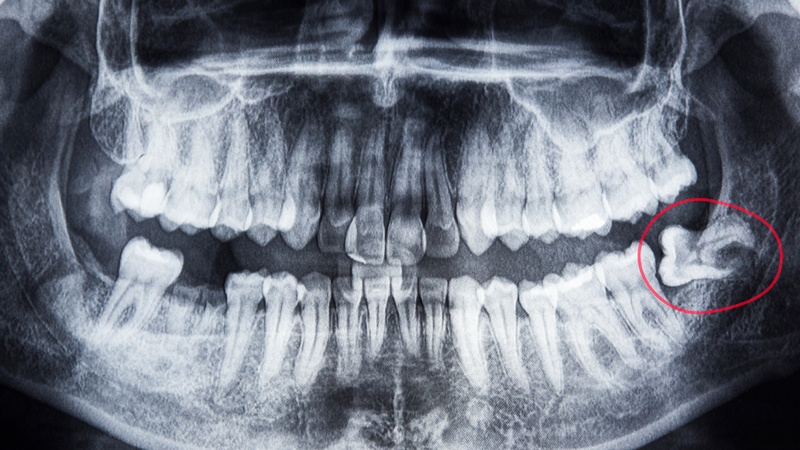

Trong một số trường hợp, nang thân răng chỉ được phát hiện tình cờ khi chụp X-quang răng hoặc kiểm tra nha khoa định kỳ. Do đó, việc thăm khám nha khoa định kỳ rất quan trọng để phát hiện sớm các bệnh lý tiềm ẩn.

• Chụp X-quang răng: Đây là phương pháp phổ biến nhất để phát hiện nang thân răng. Hình ảnh X-quang cho thấy rõ sự xuất hiện của nang và mức độ ảnh hưởng đến răng và xương hàm.